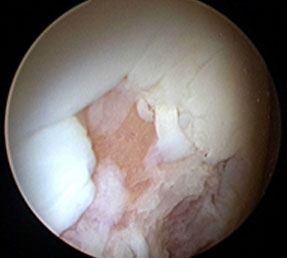

限局した比較的小さな軟骨損傷に対して効果的な方法です。軟骨損傷部の骨に非常に小さな幾つかの穴をつくることにより軟骨組織の下の骨髄を刺激し軟骨様組織の再生を促進する方法です。

マイクロフラクチャー後